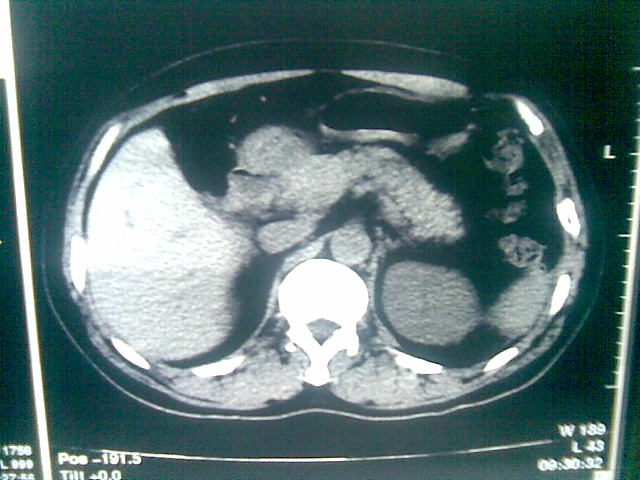

标题: CT23981:男,38岁阑尾炎术后透视胸腔积夜!做CT如下!积液包 [打印本页]

标题: CT23981:男,38岁阑尾炎术后透视胸腔积夜!做CT如下!积液包

可能与阑尾术后关系不太大,1.胸膜增厚粘连见少量气体。包裹脓气胸?左侧网膜囊脓肿?

.胸膜增厚粘连见少量气体。包裹脓气胸

左侧胸膜增厚、粘连+包裹液气胸。